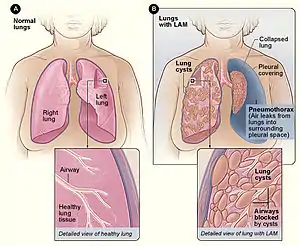

| Figure A shows the location of the lungs and airways in the body. The inset image shows a cross-section of a healthy lung. Figure B shows a view of the lungs with LAM and a collapsed lung (pneumothorax). The inset image shows a cross-section of a lung with LAM. | |